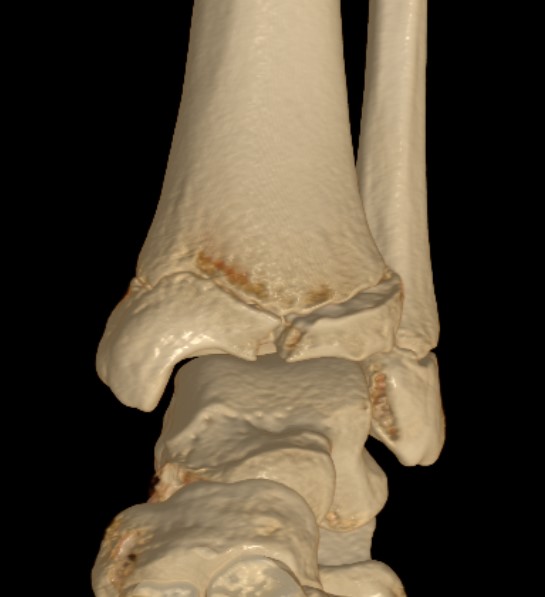

Triplanar Fracture

Definition

Fracture in coronal, sagittal and transverse planes

- crosses epiphysis

- passes through growth plate

- extends into metaphysis

Xray

AP xray: Salter-Harris type III / Tillaux

Lateral xray: Salter-Harris Type II

CT

Coronal images: Salter-Harris type III

Sagittal images: Salter-Harris type II

Axial images: 3 point star